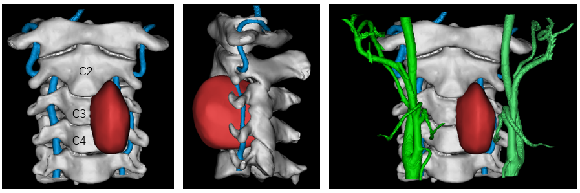

介入血管外科王昌明主任医师通过评估双侧椎动脉功能,认为小石的右侧椎动脉通畅,且为优势动脉,可以切除左侧椎动脉和相关神经根。如果术中损伤右侧椎动脉,可上台进行搭桥等方法的补救。

图4 肿瘤包饶椎动脉情况

由韦峰主刀,在全麻下采用前-后-前联合入路实施手术。肿瘤埋藏于高位颈椎,突入肌肉组织,并濒临脊髓、椎动脉、食道和气道之间,分离空间十分局促,操作过程异常小心谨慎。

缓慢拨开位于颅底旁的对侧椎动脉和血管,一点一点将周围细如发丝、错综复杂的重要神经与薄如蝉翼的肿瘤包膜剥离开,当确保肿瘤各个部分的边界充分游离后,在毫厘之间果断结扎被肿瘤包绕的左侧第三、四节颈椎神经根及椎动脉,切除侵蚀颈椎,一个足足鸡蛋大小、质地较韧的肿瘤终于被完整取出。